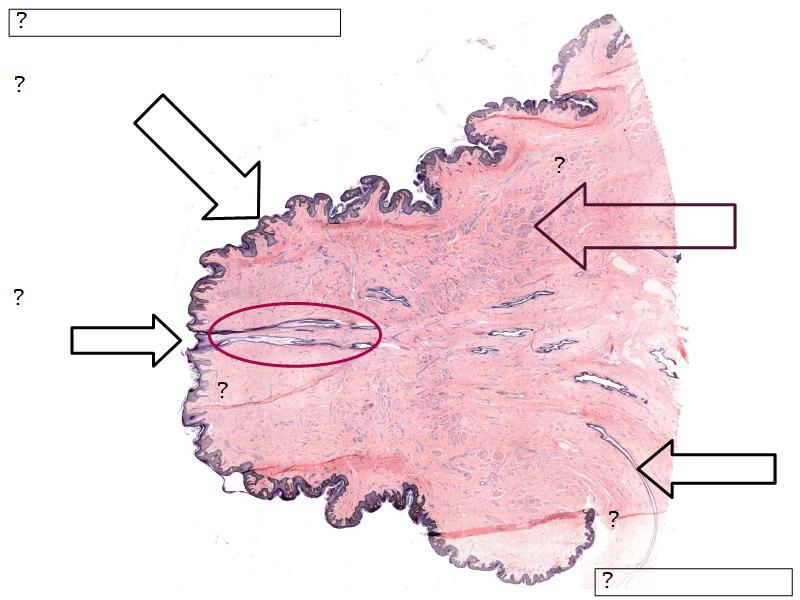

Mammary gland

Write short notes describing the structure of the mammary gland.

(5)

Mammary gland

- Compound tubuloalveolar gland

- 12 - 20 glands

- Each with own lactiferous duct

- Each with own lactiferous sinus

- Opens on skin at apex of nipple

Structures

List the structures and cells found in the mammary gland.

Structures

- Lactiferous sinuses

- Stratified squamous near opening on skin

- Stratified cuboidal other parts

- Lactiferous ducts

- Stratified cuboidal

- Myoepithelial cells

- Underlie lactiferous ducts in most areas

- Basal lamina

- Separate epithelial components from stroma

Morphology

What are the main morphological features of the nipple?

(4)

Morphology

- Covered with skin

- Consists of dense collagenous connective tissue

- Interlaced with smooth muscle fibres

- Contains openings of lactiferous ducts

Skin

- Keratinized stratified squamous epithelium

- Sebaceous glands

Stroma

- Collagenous connective tissue

- Irregular dense connective tissue

- Smooth muscle

- Fibres and bundles

- Lactiferous sinusses

- Stratified cuboidal epithelium